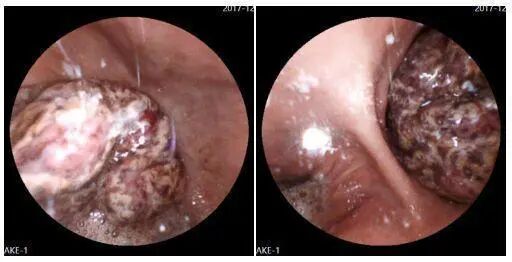

病例四: 王先生,61岁,2017年12月15号前往体检中心正常查体,使用胶囊胃镜见胃角一巨大占位性病变,经病理确诊为腺癌伴溃疡。